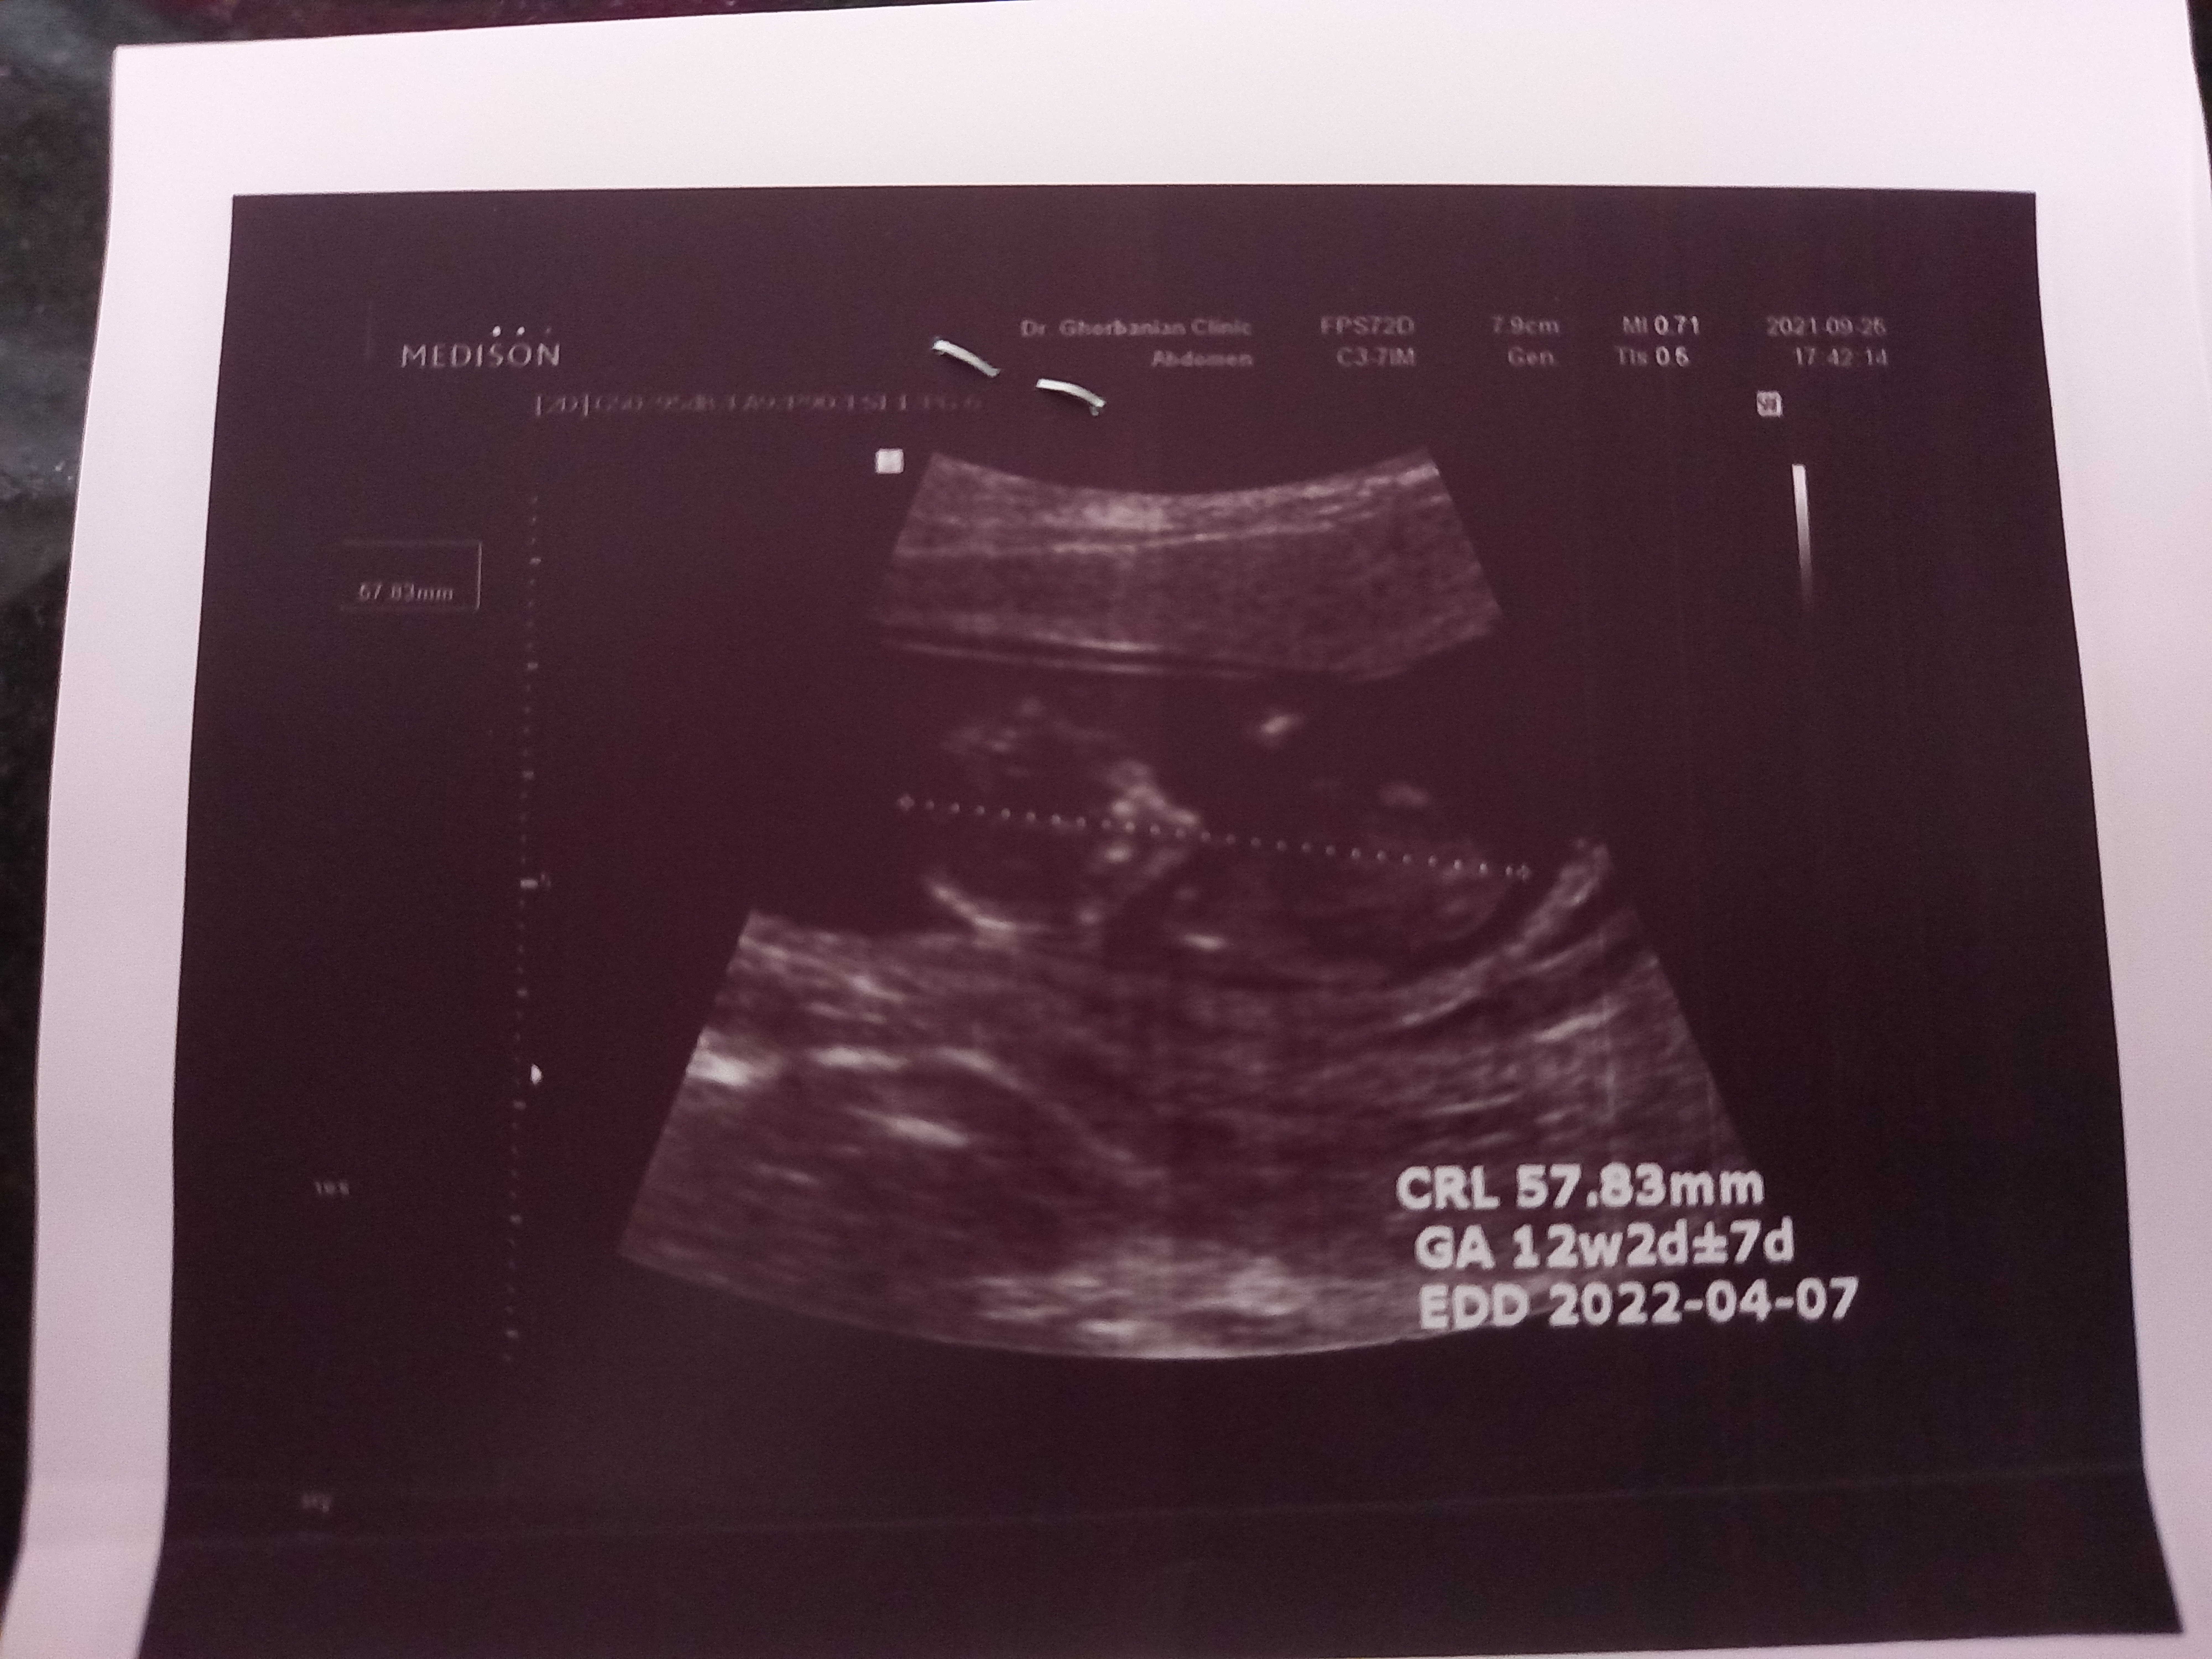

تعیین جنسیت

برای منم میگید چیه مرسی

انگار پسره 😃

مرسی عزیزم هنوز که گفته معلوم نیست🤷